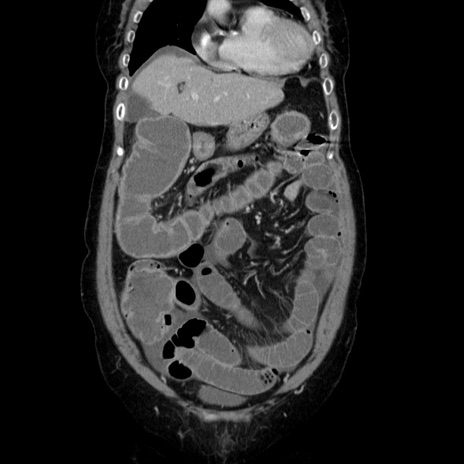

症例5(冠状断像)

【症例】70歳代女性

【主訴】お腹が張る

【現病歴】1週間くらい前から腹部膨満の自覚あり。昨日夜から増悪したため、本日救急外来受診。

【身体所見】意識清明、BT 36.5℃、BP 165/106mmHg、HR 80bpm、SpO2 98%、腹部:膨満、軟、自発痛・圧痛なし、触診にて不快感あり、腸蠕動音:減弱

【データ】WBC 12600、CRP 1.04